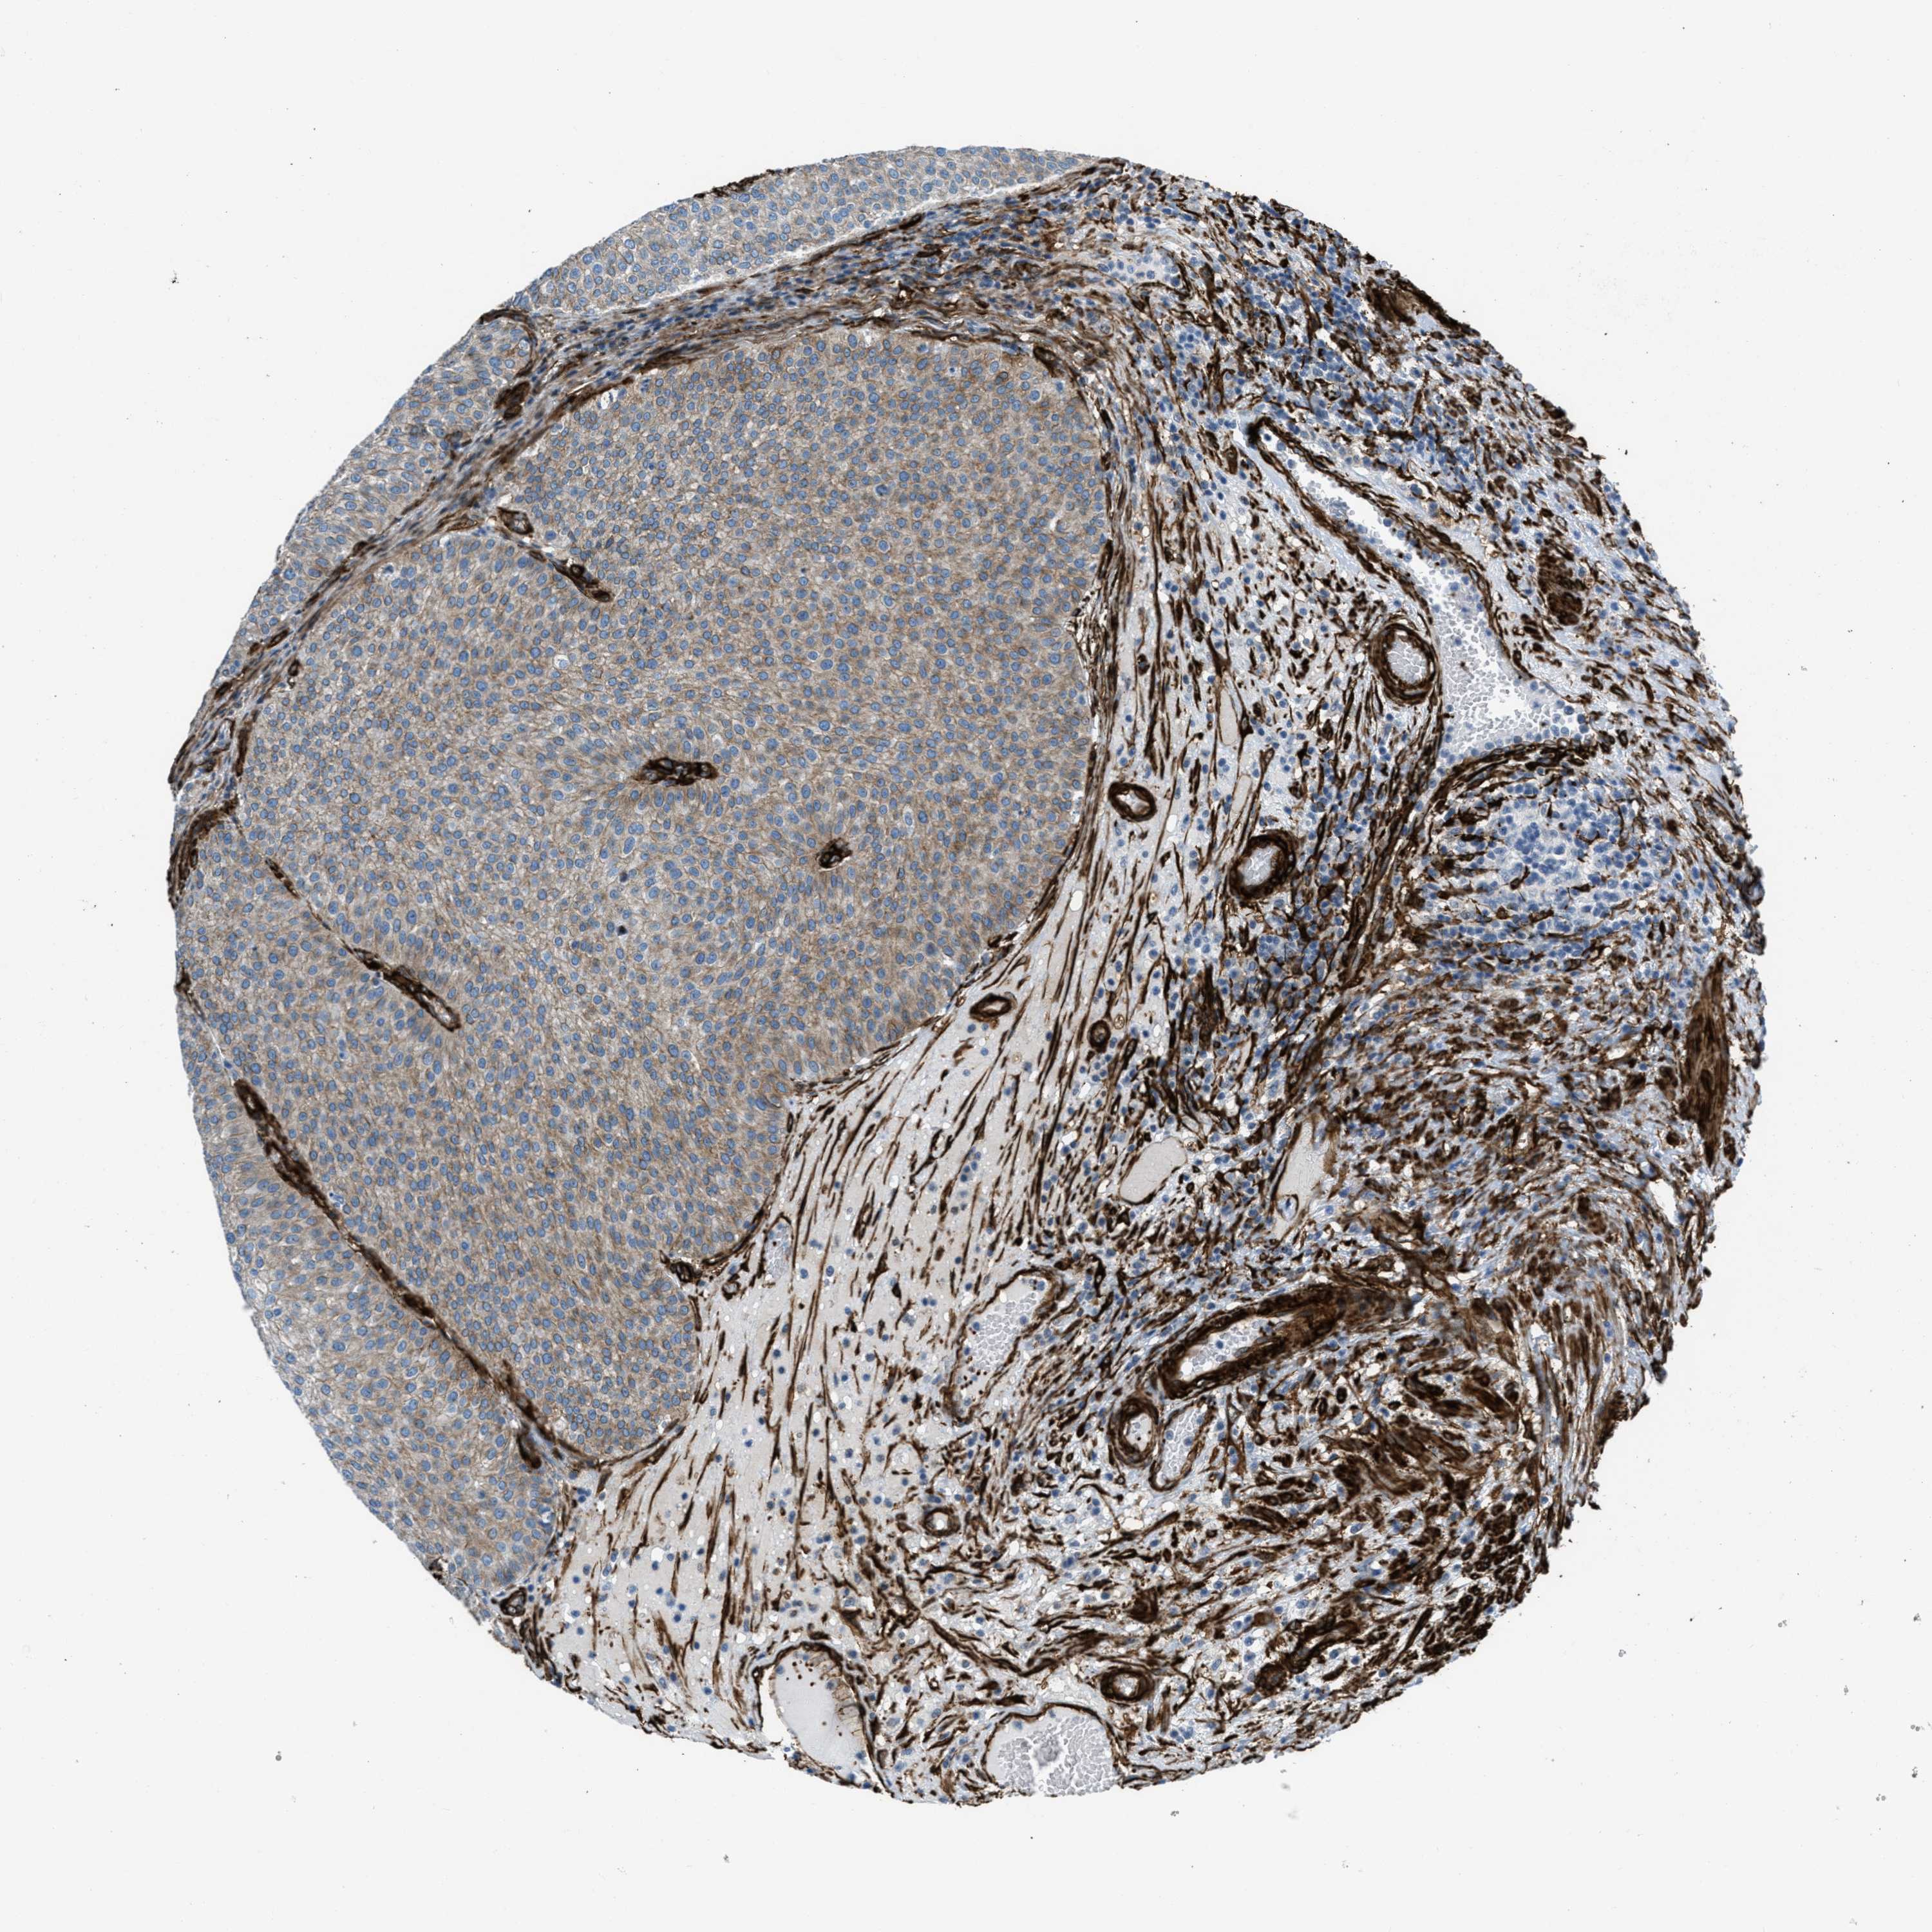

UROTHELIAL CANCER - Protein expressioni

A mouse-over function shows sample information and annotation data. Click on an image to view it in a full screen mode. Samples can be filtered based on level of antibody staining by selecting one or several of the following categories: high, medium, low and not detected. The assay and annotation is described here.

Antibody stainingi

Antibody staining in the annotated cell types in the current human tissue is reported as not detected, low, medium, or high, based on conventional immunohistochemistry profiling in selected tissues. This score is based on the combination of the staining intensity and fraction of stained cells.

Each image is clickable and will lead to virtual microscopy that enables deeper exploration of all samples and also displays staining intensity scores, fraction scores and subcellular localization as well as patient and tissue information for each sample.

Antibody HPA008066

Antibody HPA017330

Antibody CAB000006

Urothelial carcinoma, Low grade

Urothelial carcinoma, High grade